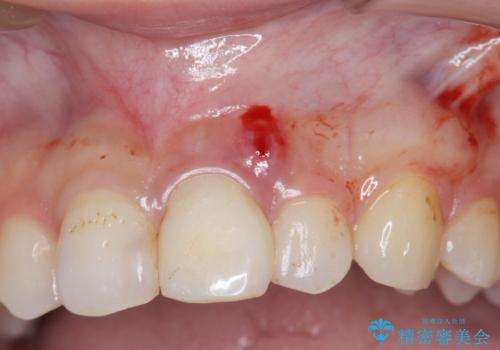

- 前歯部の歯ぐきが腫れたり、にきびのようなものが繰り返しできる。と不快症状を訴えて来院されました。

X線検査を行い診断的な小手術を行ったところ、歯に亀裂があり修復が不可能な状態であることがわかりました。